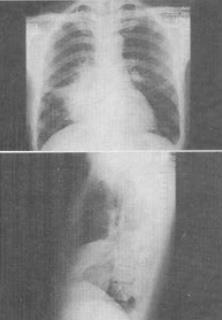

患者男,36岁,胸痛、发热2周余,X线检查如图,最可能的诊断是()。

A、右下肺炎症

B、右肺肿瘤

C、右下肺不张

D、右肺中叶综合征

E、右侧气胸

D